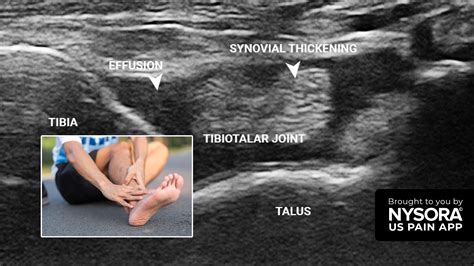

Joint effusion occurs when excess fluid accumulates in the joint space, leading to swelling and discomfort. This condition can affect any joint in the body, but it is most commonly observed in the knees, elbows, and ankles. The fluid buildup can be due to various factors, including injury, infection, or underlying medical conditions.

• Imaging Tests: X-rays, MRI, or ultrasound may be used to visualize the joint and assess the extent of fluid buildup.